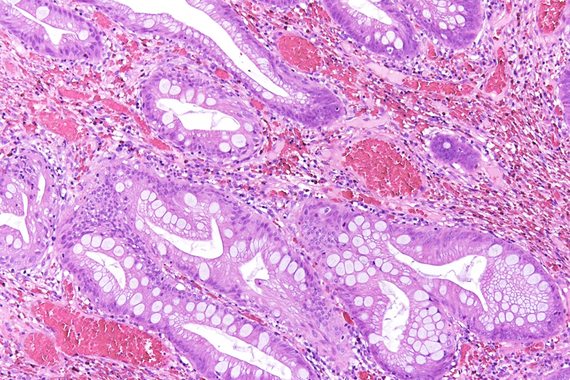

Ultrasound-guided biopsy of a pancreatic lesion in a 38-yeard-old woman (histological and cytological correlation).